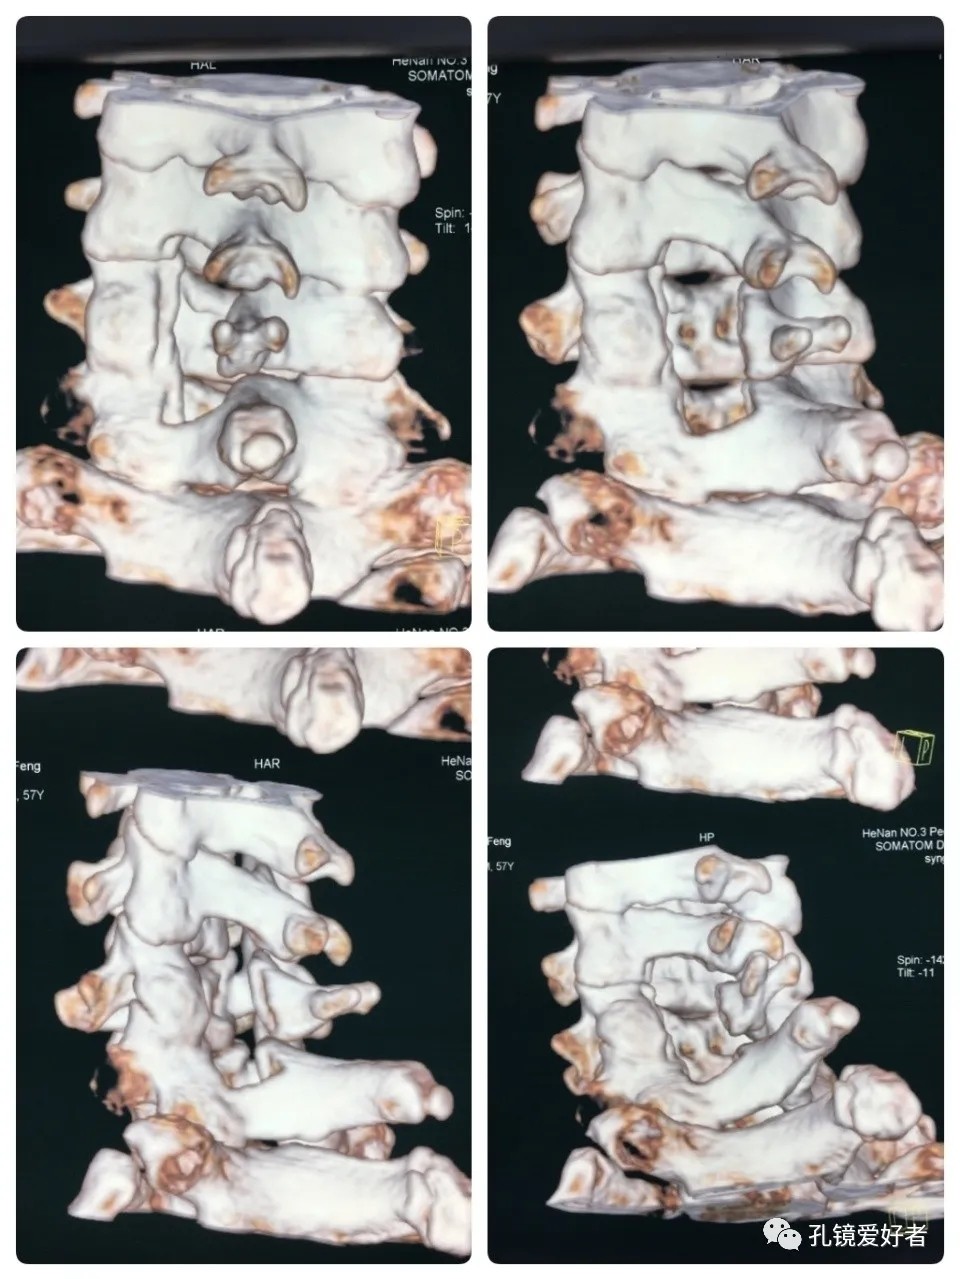

Postoperative CT Imaging

Dynamic CT Imaging

CT Imaging of 3D Reconstruction